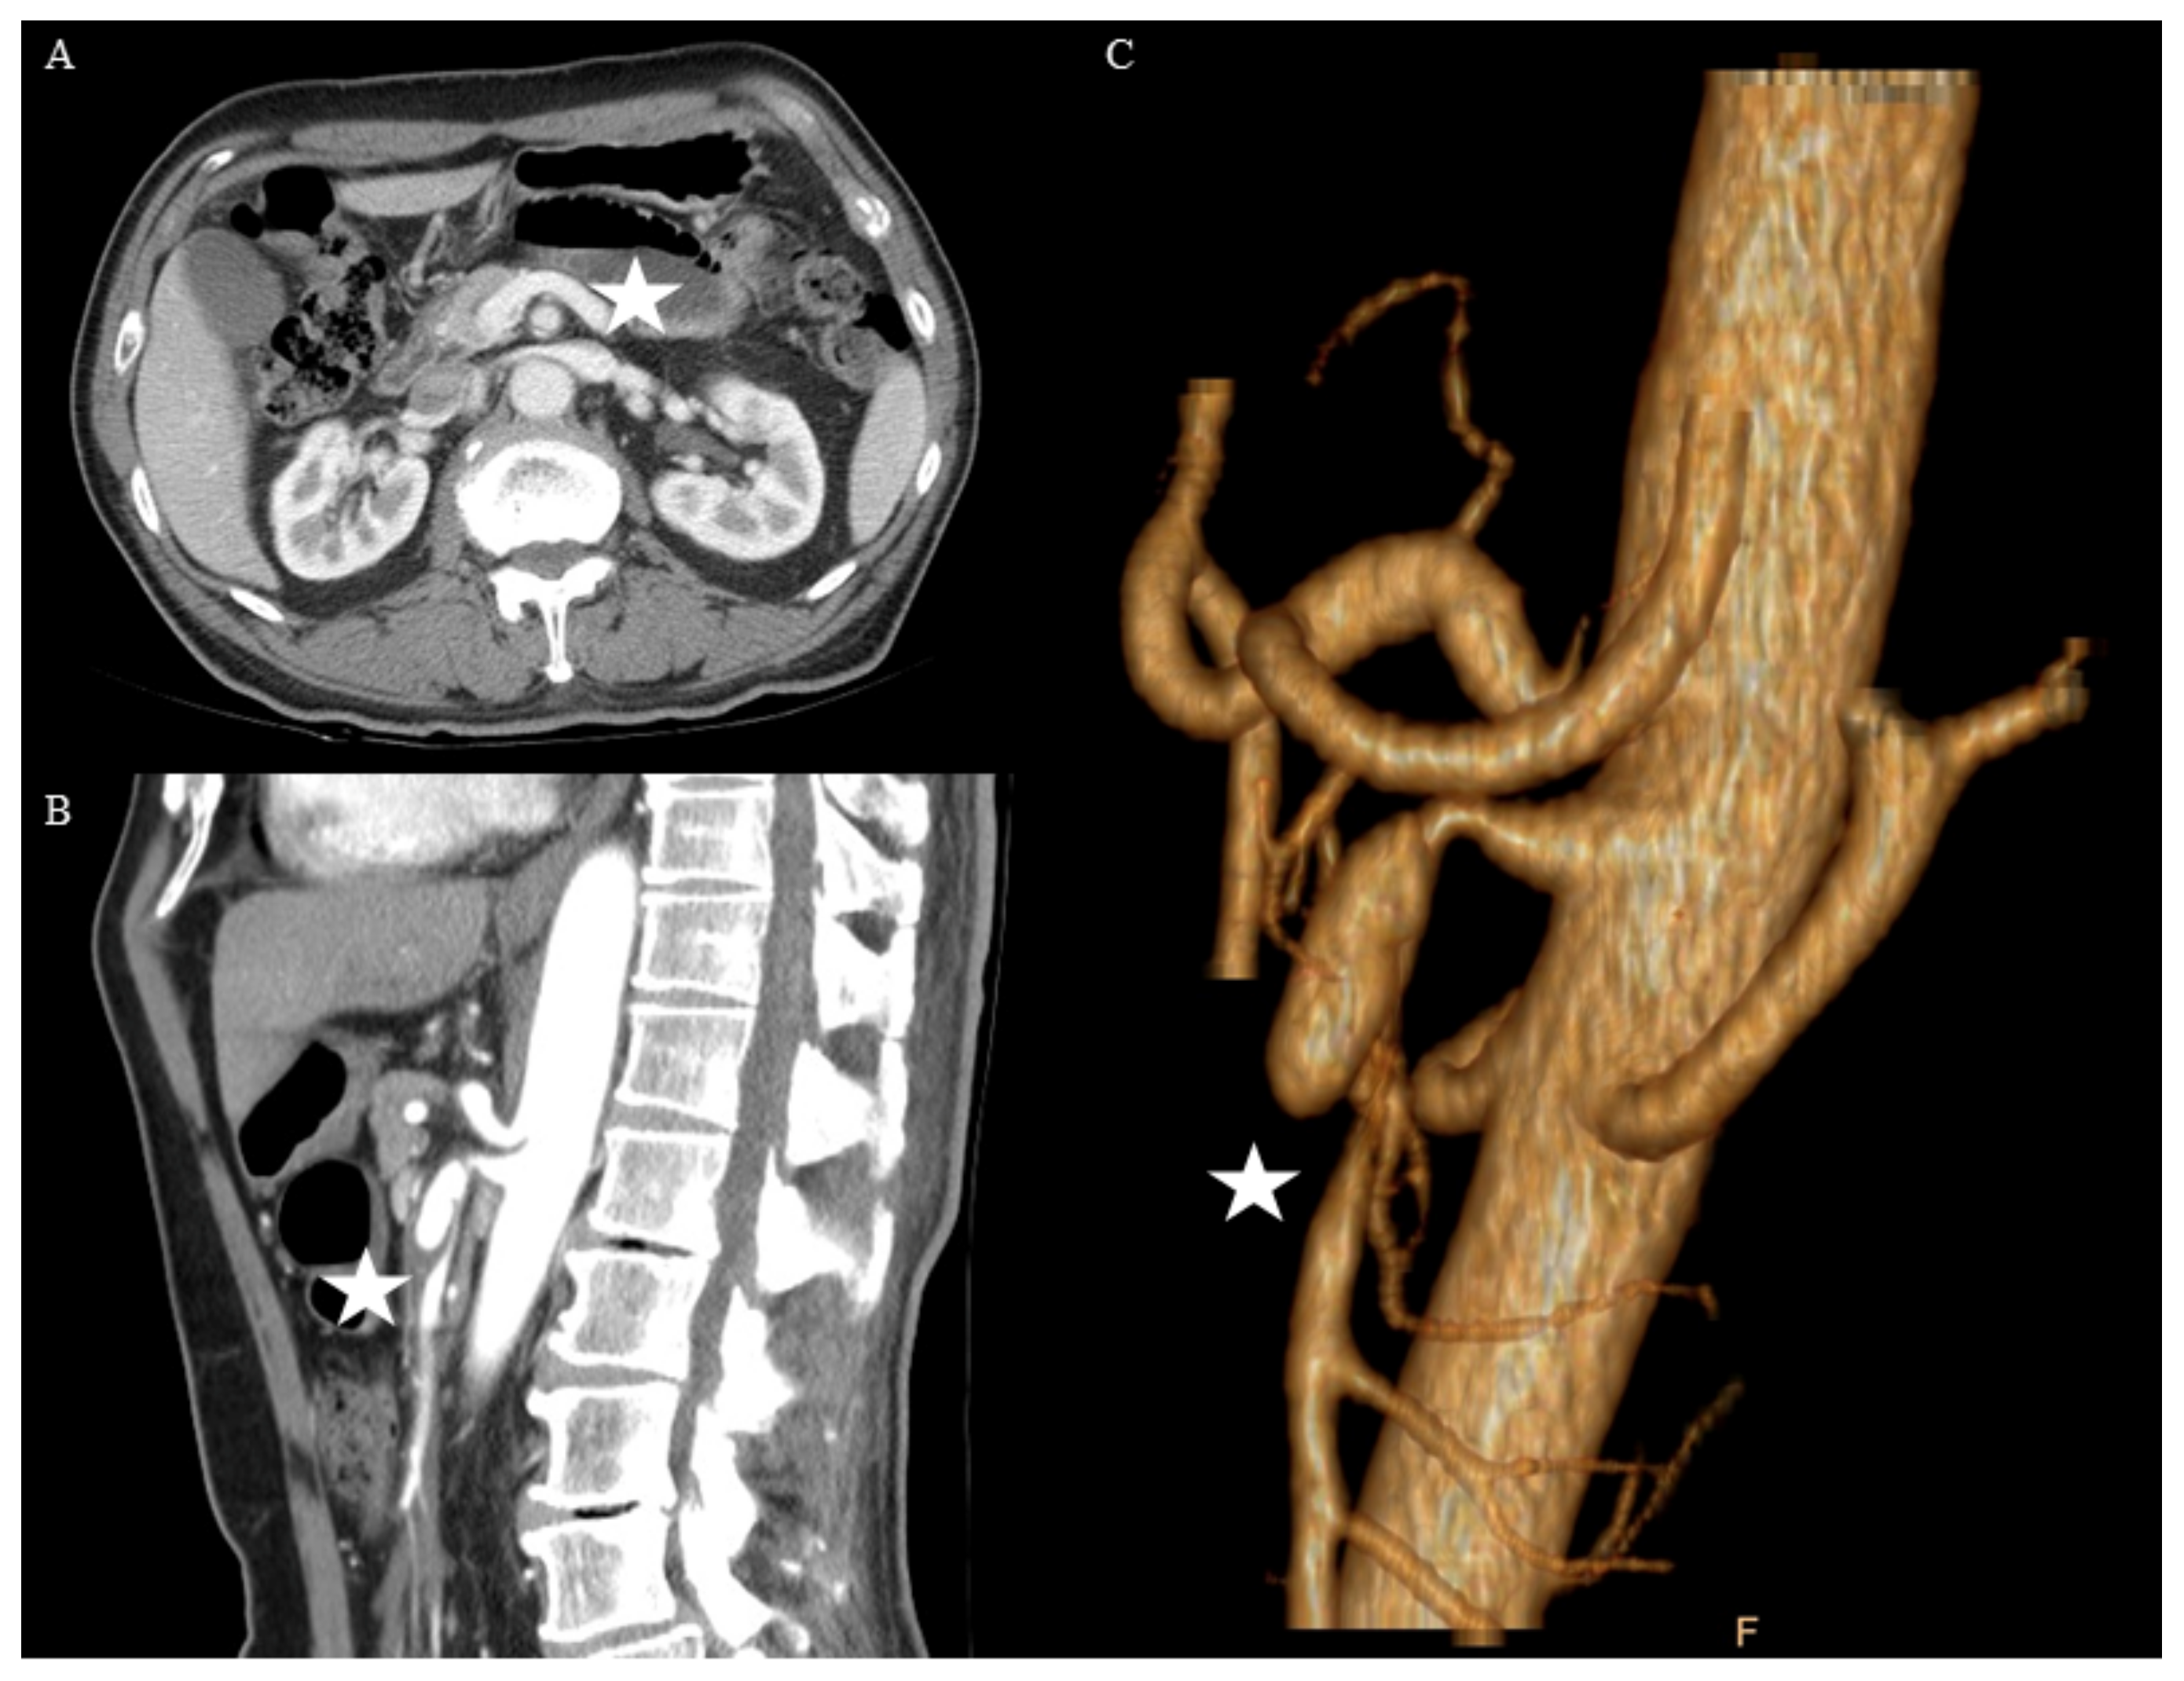

Figure 1.

This was a 66-year-old man with Yun’s IIa spontaneous isolated dissection of the superior mesenteric artery (asterisks). Computed tomography (CT) scans, (A) axial, (B) sagittal, and (C) three-dimensional, demonstrated small patent true lumen, and conservative treatment was applied first.